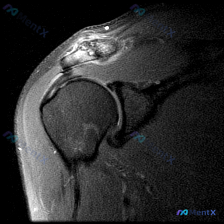

这个肩部MRI影像的核心发现,到底是盂唇病变还是肩袖撕裂?

看到一个肩部MRI(冠状位)的病例资料,用户最初的问题是关于「盂唇病理」,但整理的分析报告里有几个点挺值得讨论的:

先放影像的关键发现:

- 冈上肌腱连续性中断,断端回缩,伴冈上肌肌腹萎缩、脂肪浸润

- 肩峰下-三角肌下滑囊积液,肩峰下间隙变窄,肱骨头上移

- 肱骨头大结节下方骨髓水肿

- 盂唇形态模糊,关节间隙有积液

大家第一眼看完这些信息,最支持的诊断方向是什么?会不会有人只盯着「盂唇形态模糊」就先考虑盂唇撕裂?